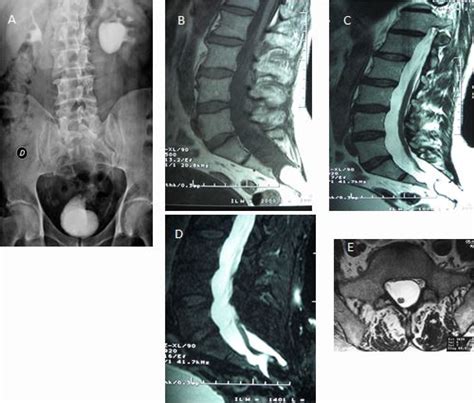

When Tethered Cord Symptoms are suspected, physicians utilize advanced imaging techniques to confirm the diagnosis. A physical examination is the first step, where doctors look for the previously mentioned skin markers or gait irregularities. To gain a clearer picture, the following diagnostic tools are commonly used:

• Magnetic Resonance Imaging (MRI): This is the gold standard for visualizing the spinal cord and determining the location of the tethering point.

• Ultrasound: Often used in infants because their vertebrae have not yet fully ossified, providing a quick, radiation-free image of the cord.